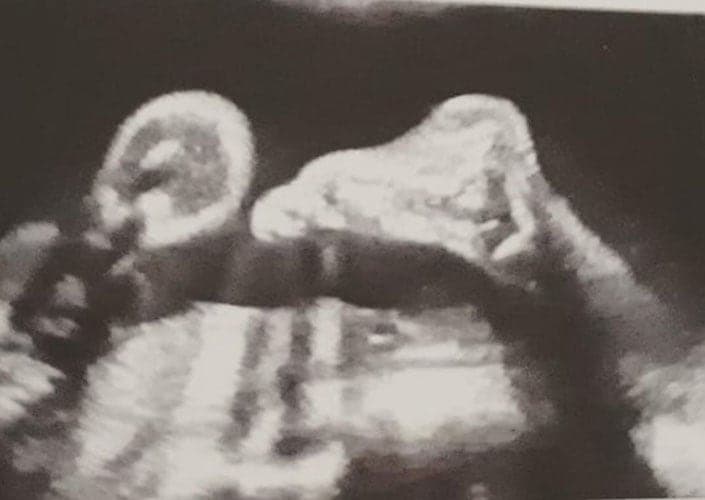

Ultraschallbilder aus dem 2. Trimester (13. bis 28. SSW)

Im 2. Trimester bekommt man oft die schönsten „Ganz-Körper“ Ultraschallbilder. Das Baby ist nun so groß, dass man alles gut erkennen kann und noch nicht zu groß, so dass es noch ganz auf das Bild passt. In dieser Zeit lässt sich meist das Geschlecht bestimmen, wobei manche Babys es einfach nicht preis geben wollen und sich immer so drehen, dass man nichts erkennen kann.